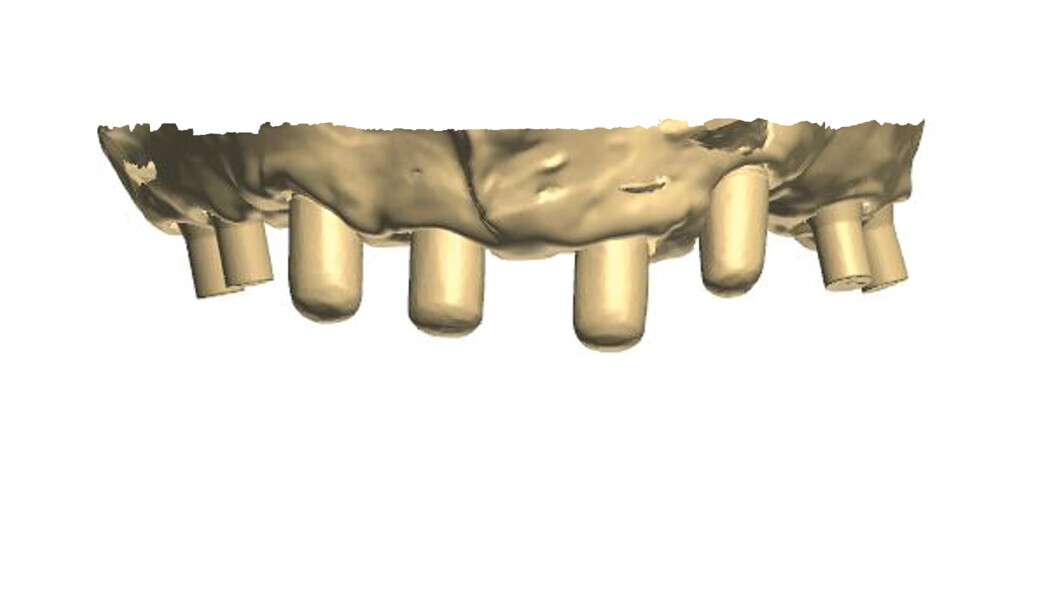

Fig. 5: Design of the framework visible from the palatal side. Visible abutments prior to the placement of telescopic crowns at the frontal section with abutments to be attached by

means of screws at the lateral section.